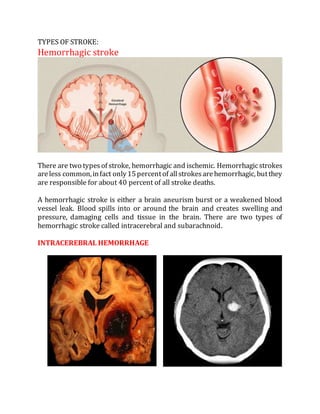

There are two typesof stroke, hemorrhagic and ischemic. Hemorrhagicstrokes

areless common,infact only15percentof allstrokesarehemorrhagic, butthey

are responsible for about 40 percent of all stroke deaths.

A hemorrhagic stroke is either a brain aneurism burst or a weakened blood

vessel leak. Blood spills into or around the brain and creates swelling and

pressure, damaging cells and tissue in the brain. There are two types of

hemorrhagic stroke called intracerebral and subarachnoid.

INTRACEREBRAL HEMORRHAGE